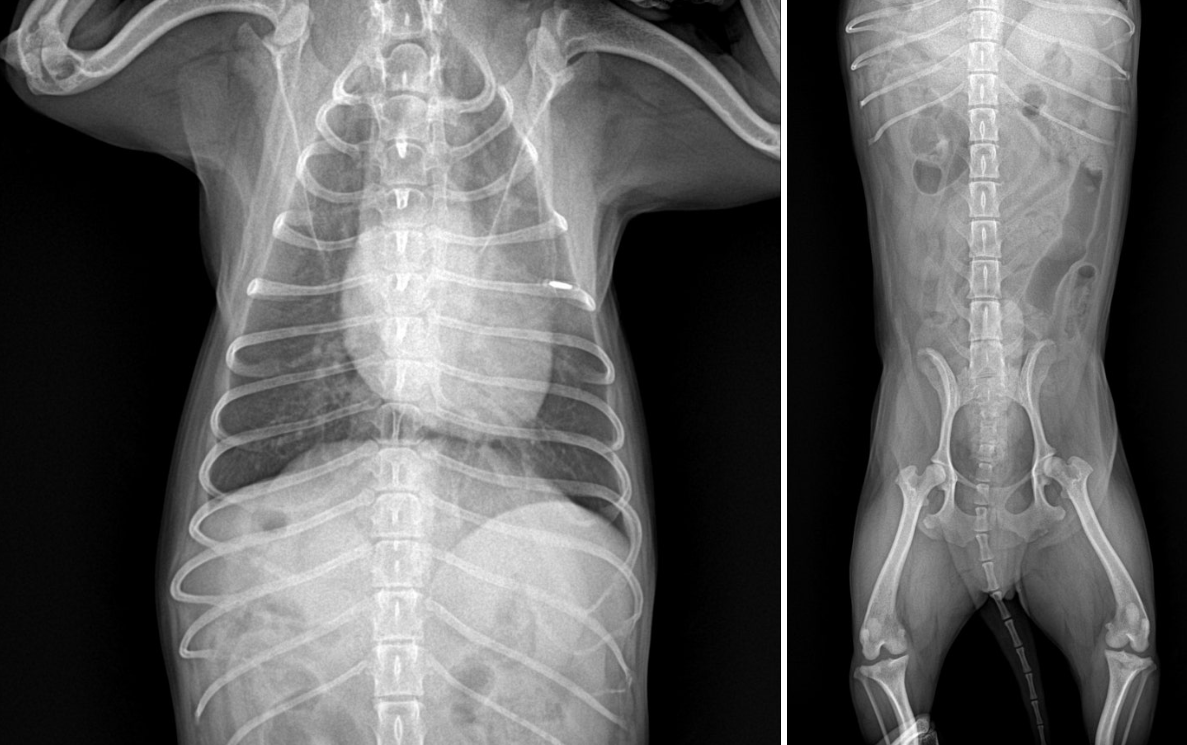

3️⃣ 방사선 검사(X-ray) 결석의 위치와 크기를 확인하는 기본 검사입니다.

대부분의 결석은 방사선에서 확인되지만, 종류에 따라 잘 보이지 않는 경우도 있습니다.